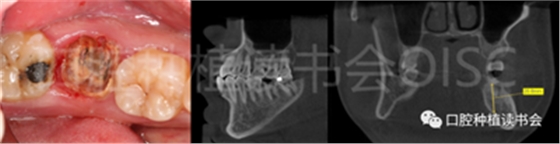

患者為70歲女性,右下后牙樁核冠因遠中牙根縱裂脫落,全身健康狀況良好,輕度骨質(zhì)疏松??趦?nèi)檢查:47殘根,遠中根縱裂,部分根面已腐至齦下2mm,叩(++),松(-);48近中傾斜阻生,咬合關系、修復間隙及牙周情況正常(圖12)。

圖12 遠中根縱裂及根面齲導致47殘根無法保留。

術前CBCT(美亞光電)檢查:47根分叉下方骨高度及骨寬度滿足即刻種植要求(圖13)。

圖13 47根分叉區(qū)骨寬度及骨高度(與下頜神經(jīng)管之間的距離)滿足即刻種植要求。